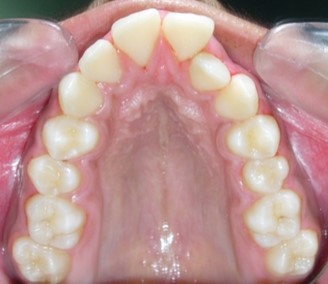

Figure 1g.Pre-treatment intra-oral-Upper occlusal

Pre-treatment intra-oral-Upper occlusal

The maxillary arch was V-shaped with severely proclined and rotated maxillary incisors with a palatally placed 12. The mandibular arch was U-shaped with severe crowding of mandibular incisors, with 43 partially erupted and buccally placed with transpositioned 42 and 43, with 42 mesiolingually rotated, 33 distolingually rotated and 34 distolingually rotated and buccally placed.

Severe increase in overjet and deep bite were both observed. The maxillary midline coincided with the skeletal midline but the mandibular midline was shifted to the right side by 1 mm. Bilateral maxillary posterior crossbite was also observed. On right side the molar relation was Class I and on the left side it was Class II. The canine relation was Class II on the left side and the curve of Spee was increased.